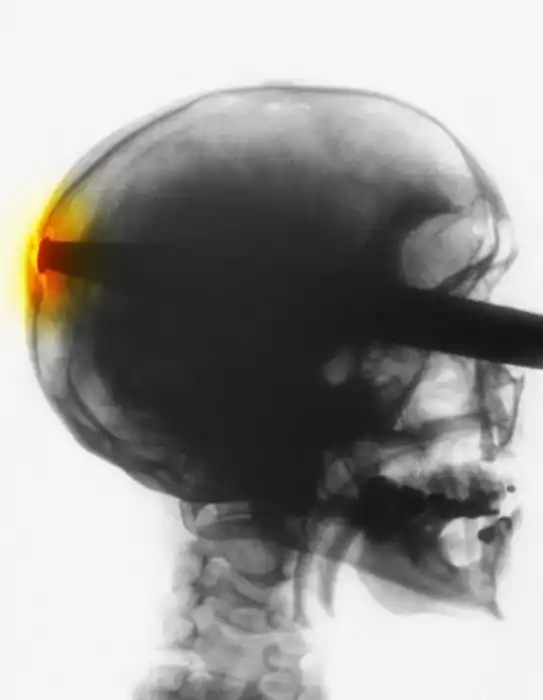

с оторванным пальцем уже не впечатляет, дурных детишек с такими травматическими ампутациями пальцев на работе насмотрелся и назашивался. Часть снимков с фатальными травмами. А с последней не понял. Ну тень средостения, ну загазованная толстая кишка, ничего патологического по костной системе не увидел, только в 10м межреберье слева хрень какая-то сеточкой.